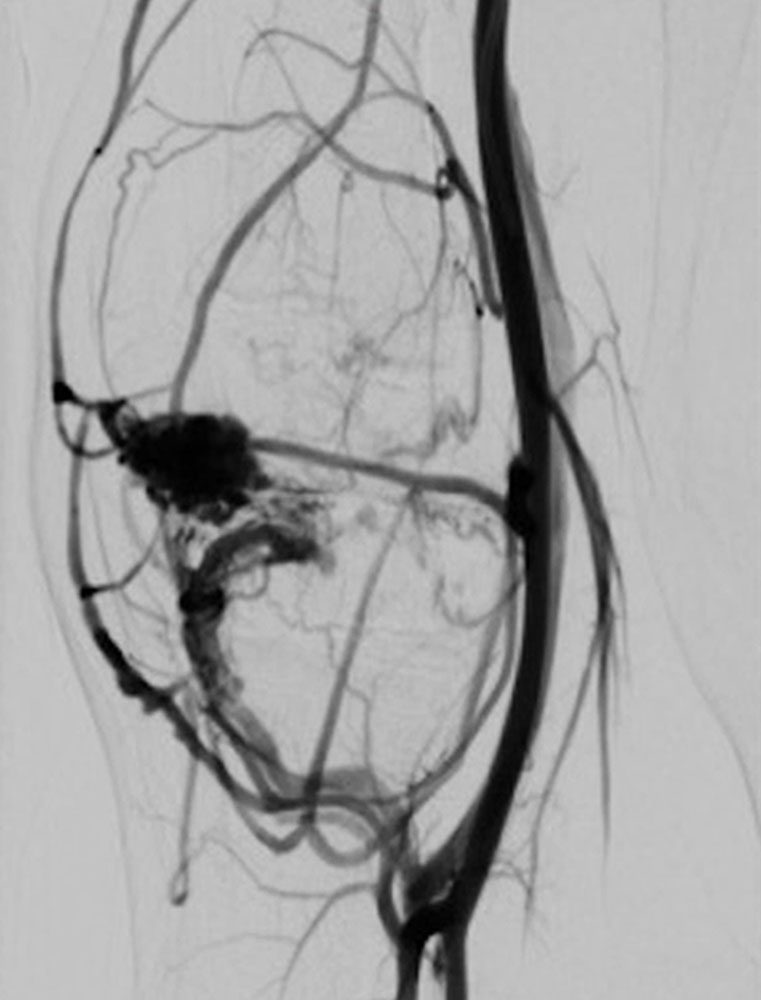

Die begleitenden Gefäßmalformationen treten nicht immer auf, sind jedoch, neben der erhöhten Wahrscheinlichkeit für das Auftreten von Tumoren, oft bestimmend für den Krankheitsverlauf beziehungsweise die Symptomatik. Relativ charakteristisch sind die als PHOST (PTEN Hamartoma Of Soft Tissue) bezeichneten, oft progredienten, umschriebenen Weichteilgewebsveränderungen, die sich histologisch als gemischte Gefäß- und Weichteilgewebsmalformationen darstellen (kapilläre, venöse und lymphatische Malformationen), die in atypisch vermehrtes, hyperplastisches Fettgewebe eingebettet sind. Die begleitenden arteriovenösen Fast-flow-Malformationen sind durch eher kugelige, intranidale oder venöse „flow-related“ Aneurysmen gekennzeichnet und rezidivieren häufig nach Behandlung.